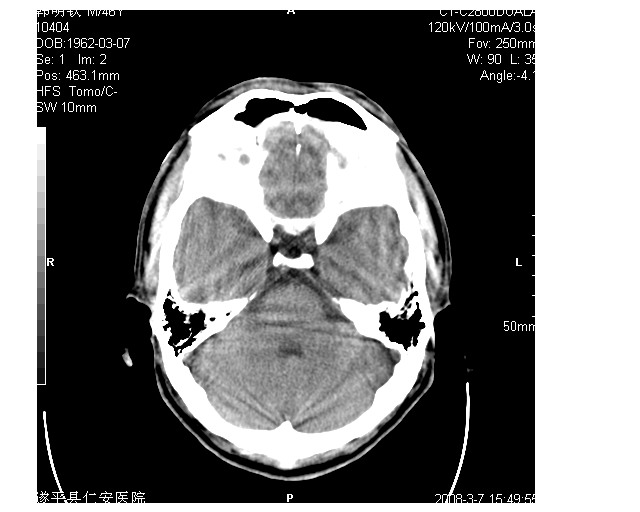

男36岁,外伤进行ct检查时发现脑实质及脑室旁多个细结节状影。是囊虫病吗?

脑内及脑室内可见多发性结节影,脑囊虫病不能除外,建议强化扫描或mri。

只看到左侧脑室内多发钙化.可以做结合补体实验啊.但未必阳性.还是隔期复查.mr 也未必定啊.